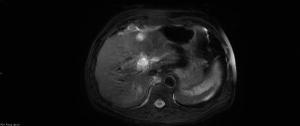

An 83-year-old man was diagnosed with multiple low-grade transitional cell carcinomas over a 6-year period. A surveillance cystoscopy in year 7 showed high-grade noninvasive papillary urothelial carcinoma in the bladder trigone. A CT urogram showed a soft-tissue mass with diffuse enhancement in the lower pole of the left kidney, concerning for malignancy.